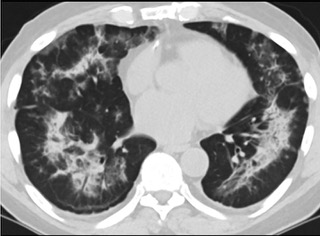

疑點(diǎn)一,電子煙患者的CT影像和臨床表現(xiàn)并不具有特異性。所謂美國電子肺炎患者,其實(shí)是對沒有其他合理診斷證據(jù)、吸食電子煙肺炎患者的統(tǒng)稱。這些患者在病發(fā)前90天內(nèi)吸食了電子煙,尤其值得注意的是,部分患者的CT影像特征和臨床表現(xiàn)與病毒性肺炎患者極其相似。

中、下肺軸位CT平掃顯示毛玻璃樣混濁伴胸膜下保留。(同一病人CT影像)